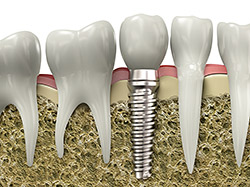

Implant Restoration

If you have missing teeth, it is

crucial to replace them. Without all your teeth, chewing and eating can

destabilize your bite and cause you discomfort. When teeth are missing, your

mouth can shift and even cause your face to look older. Implants are a great

way to replace your missing teeth, and if properly maintained, can last a

lifetime!

An implant is a new tooth made of metal and porcelain that looks just like your natural tooth. It’s composed of two main parts: One part is the titanium implant body that takes the place of the missing root, and the second part is the tooth-colored crown that is cemented on top of the implant. With implant treatment, you can smile confidently knowing no one will ever suspect you have a replacement tooth.

In addition to tooth replacement, implants may be used to anchor dentures, especially lower dentures that tend to shift when you talk or chew. For patients with removable partial dentures, implants can replace missing teeth so you have a more natural-looking smile.